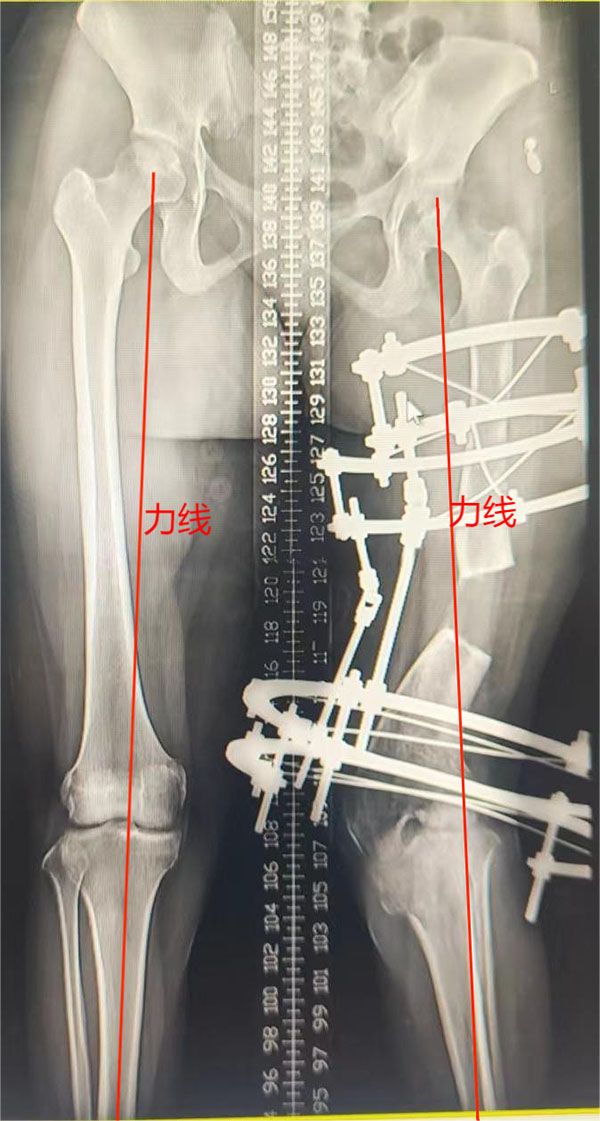

第二步:经过第一步的治疗,左下肢外翻畸形基本纠正,力线恢复,尽早拆除Illizarov架,予行切开钢板内固定术。

术后半年,力线恢复